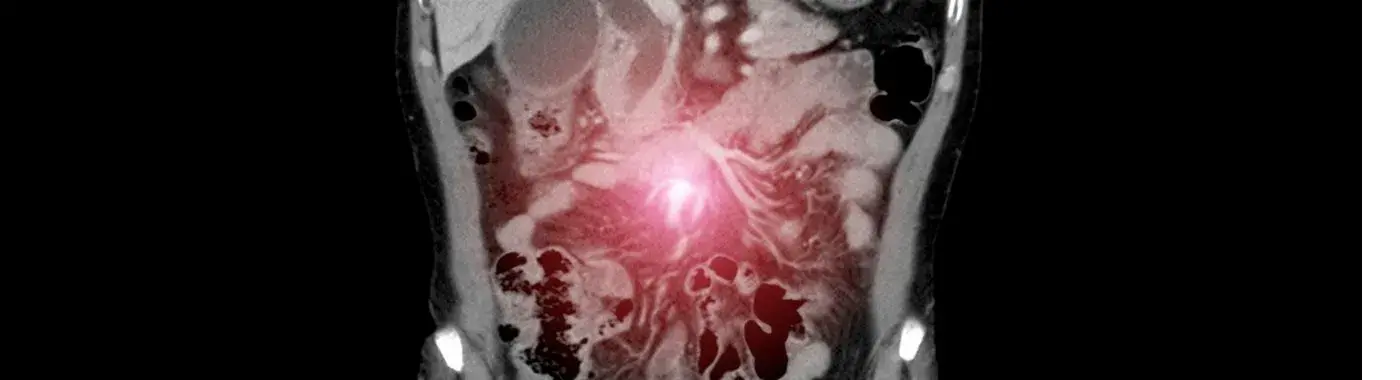

• Imaging tests: CT scan or MRI shows tumor size and spread and a detailed image of the soft tissues, PET scan detects active cancer areas throughout the body.